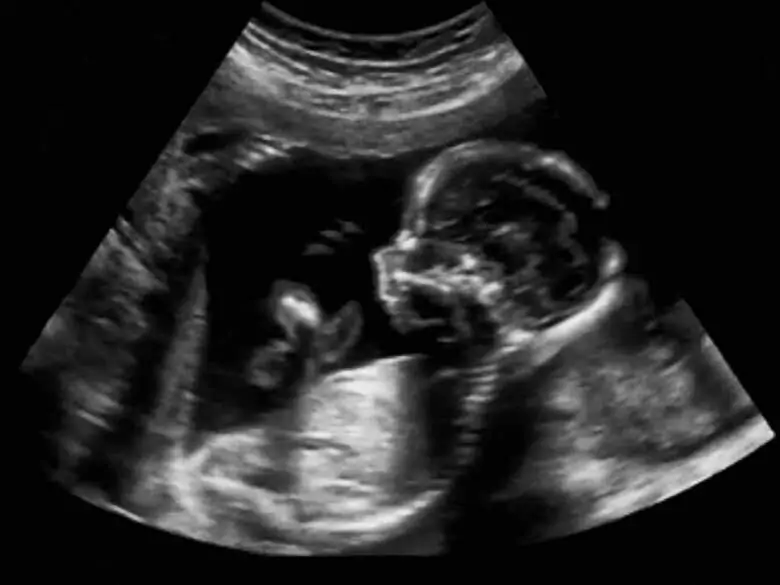

Les tests prénataux jouent depuis longtemps un rôle important en gynécologie et en obstétrique, mais de nos jours, leur valeur ne cesse d'augmenter en raison du fait que de plus en plus de femmes tombent enceintes tardivement. Parmi les tests prénataux, on distingue les tests invasifs et les tests totalement non invasifs. Quels sont les tests exacts qui sont effectués dans le cadre du diagnostic prénatal et quand chacun d'entre eux est-il utilisé ?